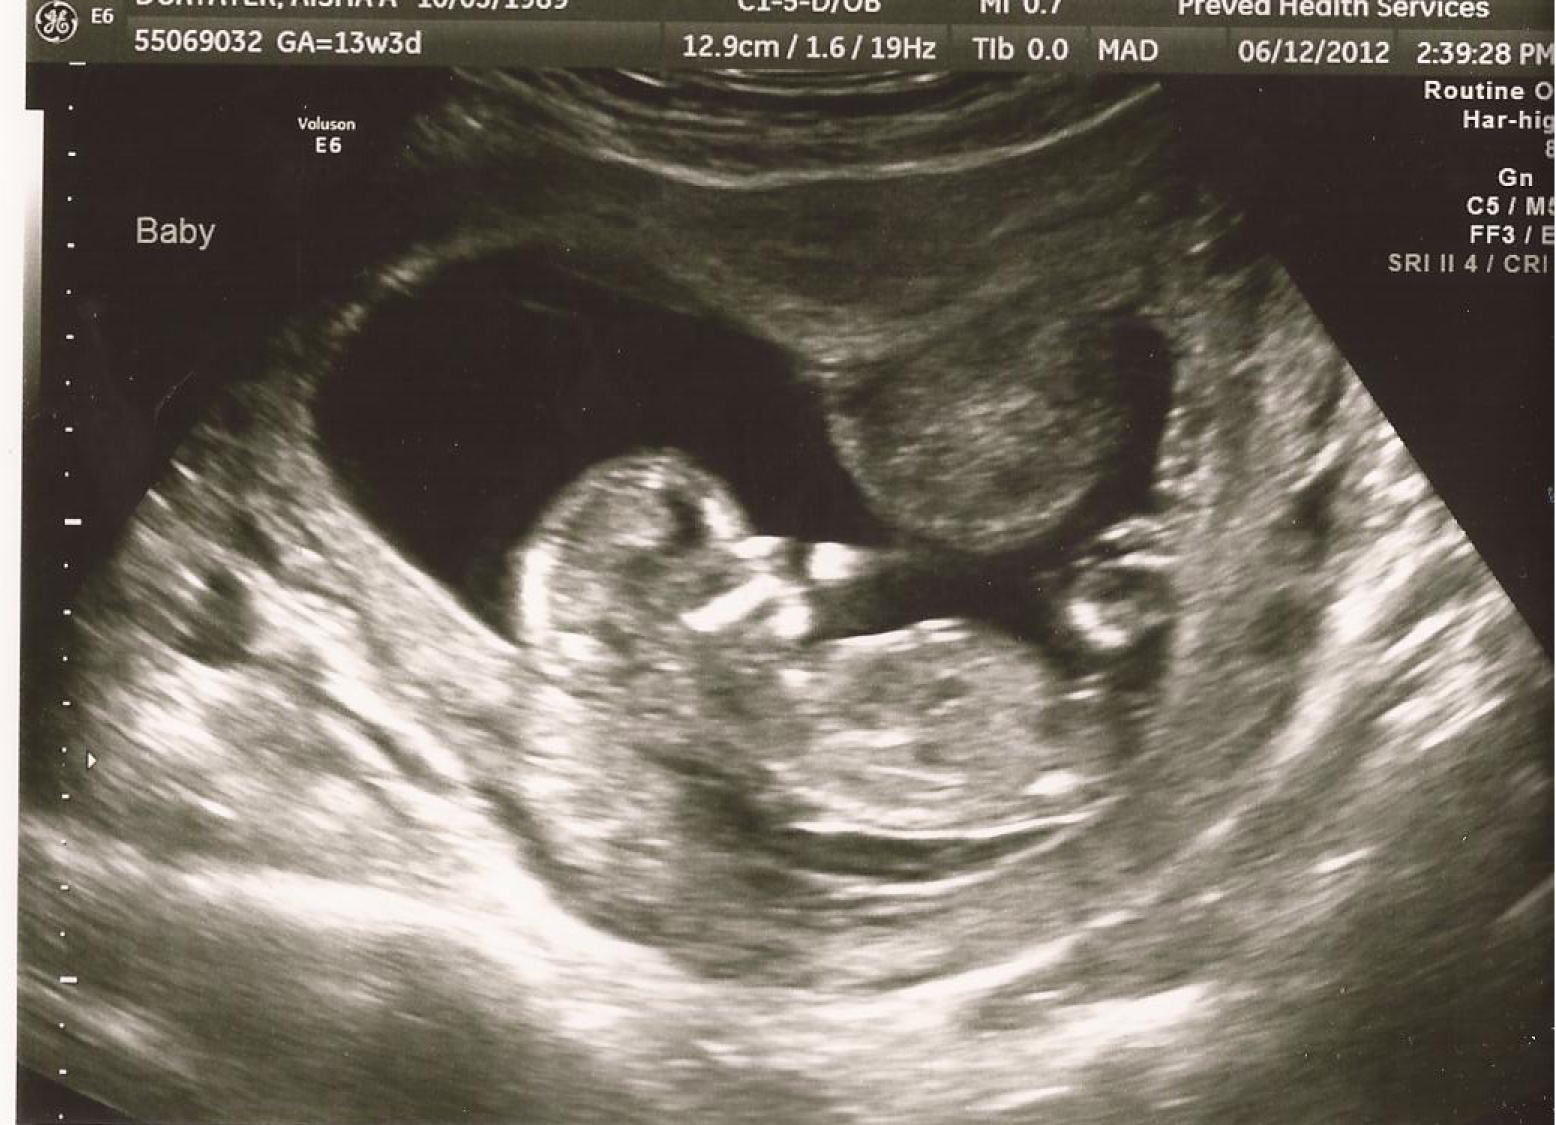

Just found out my niece is pregnant and due only 2 weeks after me!! Attachment 3099She only has the one picture. It is pretty low resolution as it was taken by her camera phone. She is going to send me a better resolution copy tonight and I will reupload it. She dated 13wk 3d. I am pretty sure of what I see but I am hoping for some tech input as rump end is touching the side of her uterus. Want to make sure what I think is the nub is. Also, if you could give some indication of how sure you are of your answer, I would really appreciate it!! Thanks!!

I am looking at the right thing, yes?? I can see the darkness of the bladder so I would think I am looking at the right one.

UPDATED - higher resolution - Maybe??? When you blow it up maybe it is not a boy??